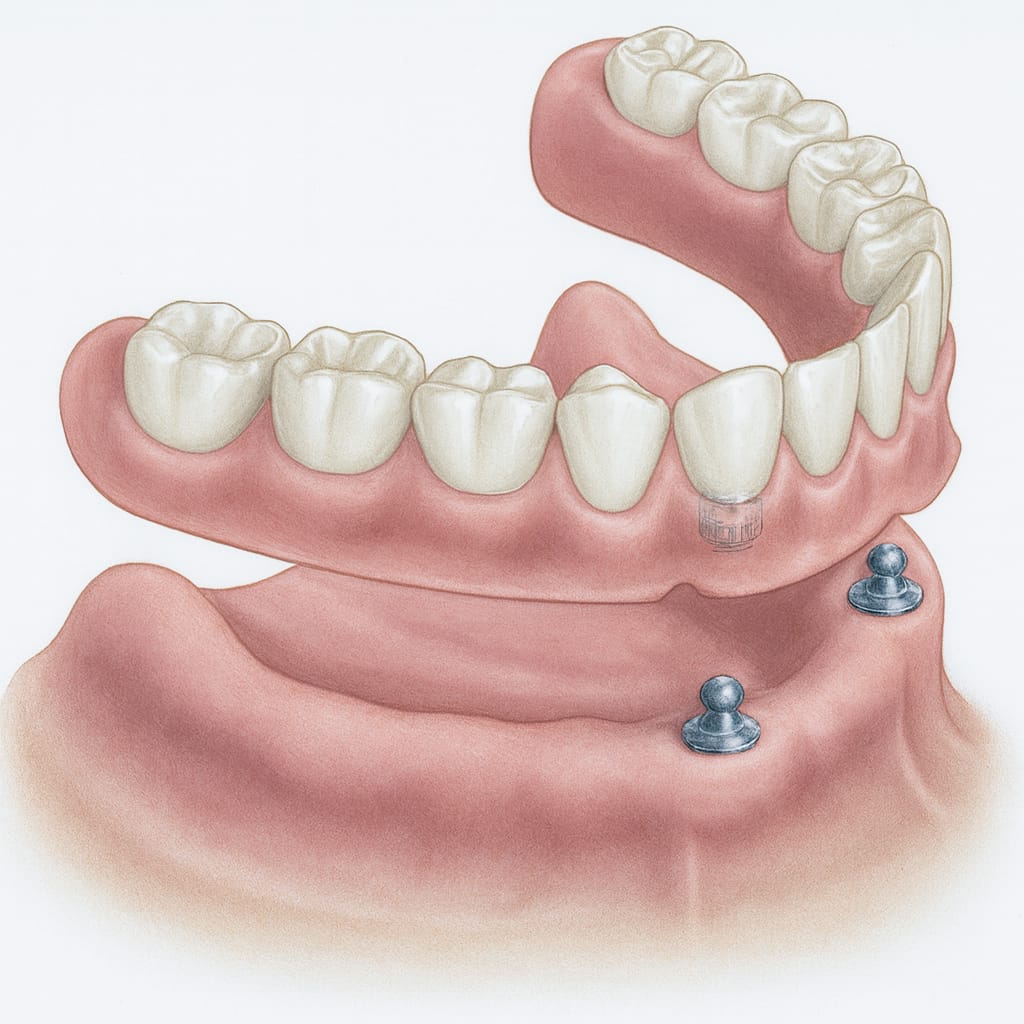

Prótesis removible sobre implante

Funciona como una prótesis removible tradicional, pero en lugar de adhesivos se ancla firmemente a la boca mediante 2 implantes dentales. Ofrece mayor estabilidad y comodidad que las prótesis convencionales.